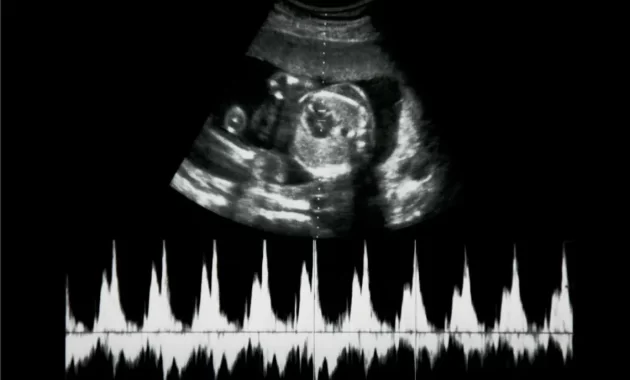

Durante las ecografías si se puede lograr detectar el corazón y los latidos pueden ser vistos a través del monitor. Sin embargo, no es hasta la semana diez de embarazo que se puede escuchar de manera clara el sonido. Dichos latidos pueden ser escuchados mediante una ecografía doppler que suele amplificar los sonidos, durante la semana diez y doce, y podemos comprobar que sus latidos son mucho más rápidos.

De igual manera mediante la misma ecografía se puede comprobar si el bebé tiene alguna anomalía cardiaca. Es con ayuda del doppler que nosotros los padres podemos escuchar los latidos del corazón del bebé, y como el ritmo cardiaco es bastante acelerado puede que sintamos que estamos escuchando varios corazones. No obstante, es el médico que se encargará de decir si nos encontramos a la espera de un bebé o dos.